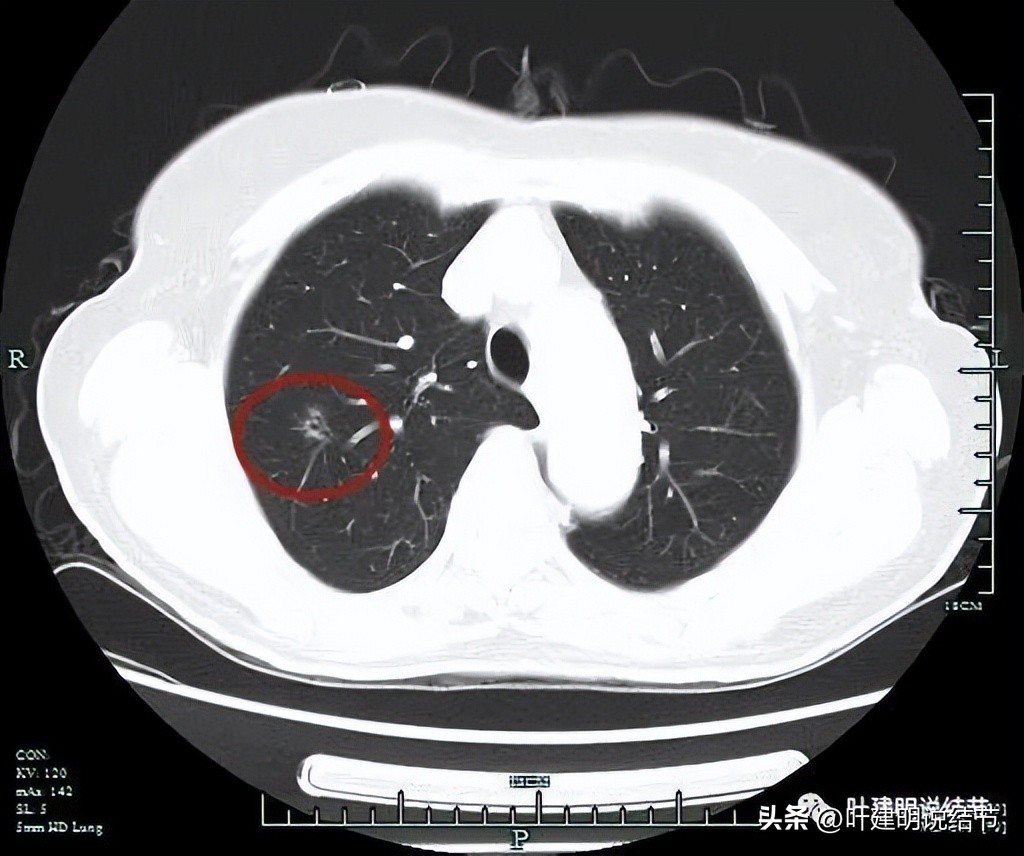

非薄层扫描显露右上叶略显模糊的磨玻璃结节,中间有小空泡的样子,边缘不平显得有毛刺样征,密度不均匀。